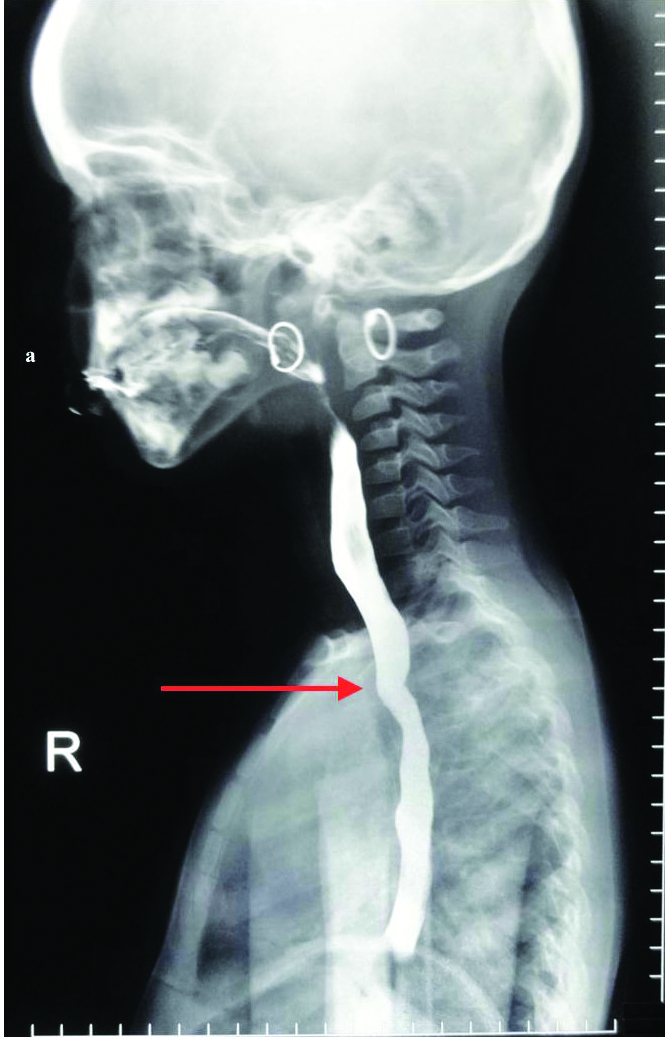

The twins were monozygotic and were weaned unsuccessfully at four months of age with semisolids. The first set of investigations included indirect and direct laryngoscopy, upper oesophago gastroduodenoscopy and oesophageal barometry but all test results were inconclusive. Computed Tomography (CT) and Magnetic Resonance Imaging (MRI) were also done and found to be inconclusive. Echocardiography was done to rule out any cardiac defects and was found to be normal. Finally, barium oesophagogram showed constant narrowing of the oesophagus at the level of the aortic arch without any evidence of mucosal irregularity. The narrowing had an oblique orientation from inferior left to superior right on the posterior aspect of the oesophagus. This was consistent with extrinsic compression by a retro-oesophageal aberrant right subclavian artery in both the patients [Table/Fig-1a,b]. Based on the above findings, operative repair was advised.

Spot film from barium oesophagogram showed constant narrowing of the oesophagus at the level of the aortic arch without any evidence of mucosal irregularity. The narrowing had oblique orientation from inferior left to superior right on the posterior aspect of the oesophagus. This was consistent with extrinsic compression by a retro-oesophageal aberrant right subclavian artery.